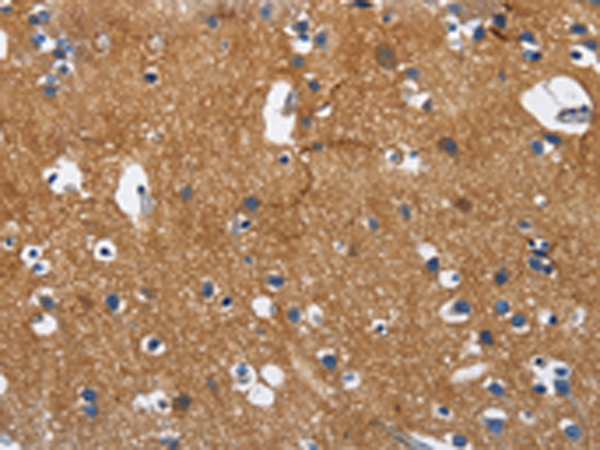

分类: 科研抗体货号: P08090别名: BIgR; NECL1; TSLL1; IGSF4B; Necl-1; synCAM3应用: IHC反应种属: Human, Mouse, Rat